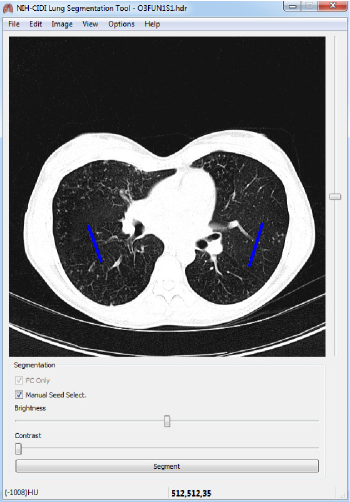

The algorithm driving the CIDI-Lung-Seg is summarized below; herein, we provide a brief summary of the algorithm. The initial lung parenchyma extraction is performed by adapting the fuzzy-connectedness (FC) image segmentation algorithm [9, 10]. The initial phase consists of two primary stages: (i) seed selection for FC, and (ii) FC segmentation. The CIDI-Lung-Seg software can identify seed locations automatically as well as it allows the user to manually select them if desired (Fig. 1). These two steps are explained in the following subsections.

Refer to caption

Figure 1: Manual seed selection in CIDI-Lung-Seg. Single-stroke painted line (shown in blue) are used as seeds for left and right lungs.